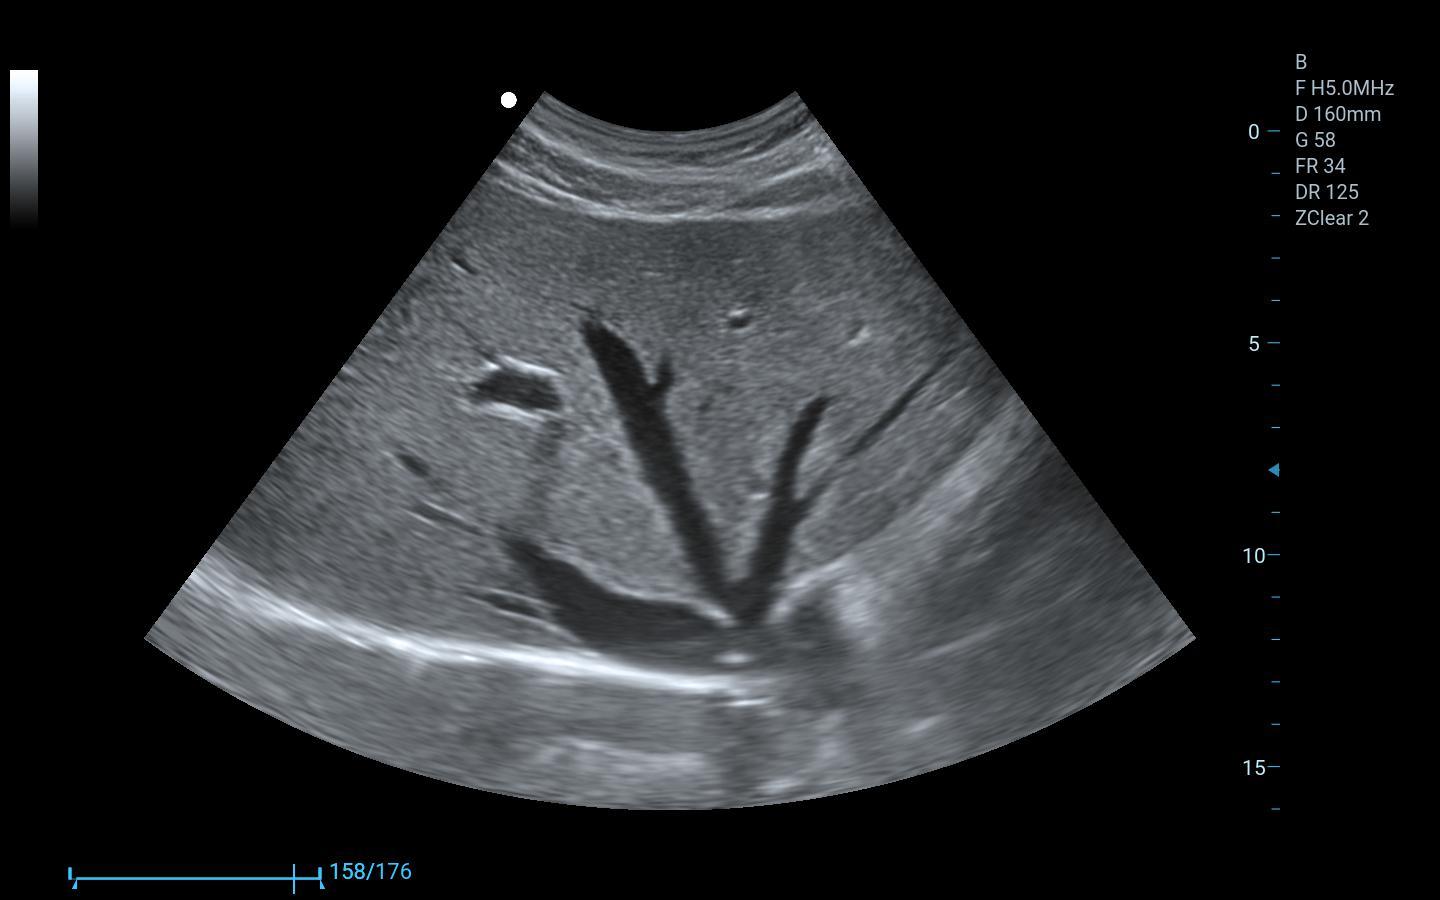

Abdomen, Obstetricia y Ginecología

Imágenes clínicas extraordinarias